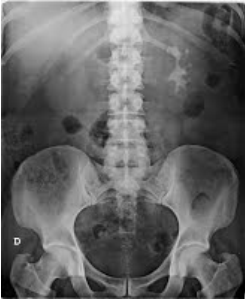

Paciente do sexo masculino, 41 anos, admitido na emergência com dor lombar à E, súbita, de forte intensidade, há 1 hora da admissão. Rx de abdômen abaixo:

A composição do achado radiológico é